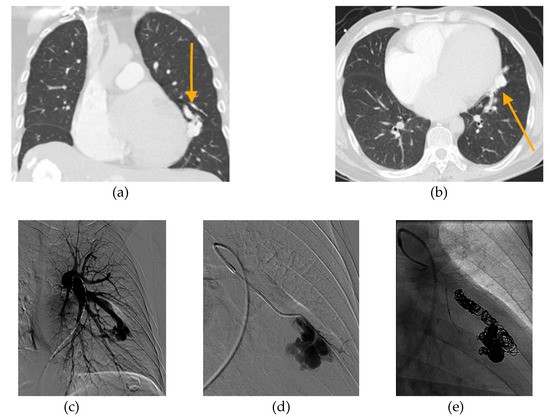

- Shimohira, M.; Kawai, T.; Hashizume, T.; Ohta, K.; Suzuki, K.; Shibamoto, Y. Pulmonary arteriovenous malformations: Current technique of transcatheter embolization and subsequent management. Interv. Radiol. 2017, 2, 116–121. [Google Scholar] [CrossRef][Green Version]

- Shimohira, M.; Kawai, T.; Hashizume, T.; Ohta, K.; Nakagawa, M.; Ozawa, Y.; Sakurai, K.; Shibamoto, Y. Reperfusion rates of pulmonary arteriovenous malformations after coil embolization: Evaluation with time-resolved MR angiography or pulmonary angiography. J. Vasc. Interv. Radiol. 2015, 26, 856–864. [Google Scholar] [CrossRef]

- Cusumano, L.R.; Duckwiler, G.R.; Roberts, D.G.; McWilliams, J.P. Treatment of recurrent pulmonary arteriovenous malformations: Comparison of proximal versus distal embolization technique. Cardiovasc. Interv. Radiol. 2020, 43, 29–36. [Google Scholar] [CrossRef]

- Hayashi, S.; Baba, Y.; Senokuchi, T.; Nakajo, M. Efficacy of venous sac embolization for pulmonary arteriovenous malformations: Comparison with feeding artery embolization. J. Vasc. Interv. Radiol. 2012, 23, 1566–1577. [Google Scholar] [CrossRef] [PubMed]

- Kajiwara, K.; Urashima, M.; Yamagami, T.; Kakizawa, H.; Matsuura, N.; Matsuura, A.; Ohnari, T.; Ishikawa, M.; Awai, K. Venous sac embolization of pulmonary arteriovenous malformation: Safety and effectiveness at mid-term follow-up. Acta Radiol. 2014, 55, 1093–1098. [Google Scholar] [CrossRef]

- Dinkel, H.P.; Triller, J. Pulmonary arteriovenous malformations: Embolotherapy with superselective coaxial catheter placement and filling of venous sac with Guglielmi detachable coils. Radiology 2002, 223, 709–714. [Google Scholar] [CrossRef] [PubMed]